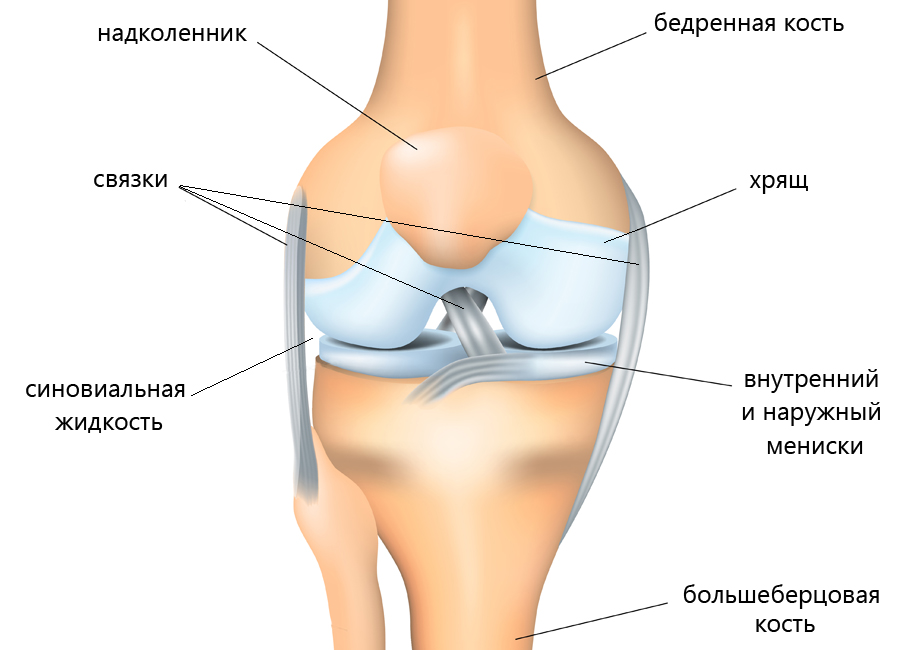

Наши суставы выполняют опорную и двигательную функции в организме. Это подвижные соединения костей скелета человека. Суставы состоят из двух костей, которые соединяются между собой суставной капсулой и связками.

Чтобы движения тела проходили плавно, суставные поверхности костей покрыты хрящом. Именно он служит для скольжения костей в суставе и способствует амортизации нагрузки.

Полость сустава заполнена густой эластичной массой — синовиальной жидкостью, которая служит дополнительным амортизатором. Ее главная задача состоит в обеспечении питания суставного хряща. Суставная капсула окружает поверхность сустава и предохраняет его от повреждений. При движениях хрящ постоянно изнашивается, но наш организм знает, как его восстанавливать.